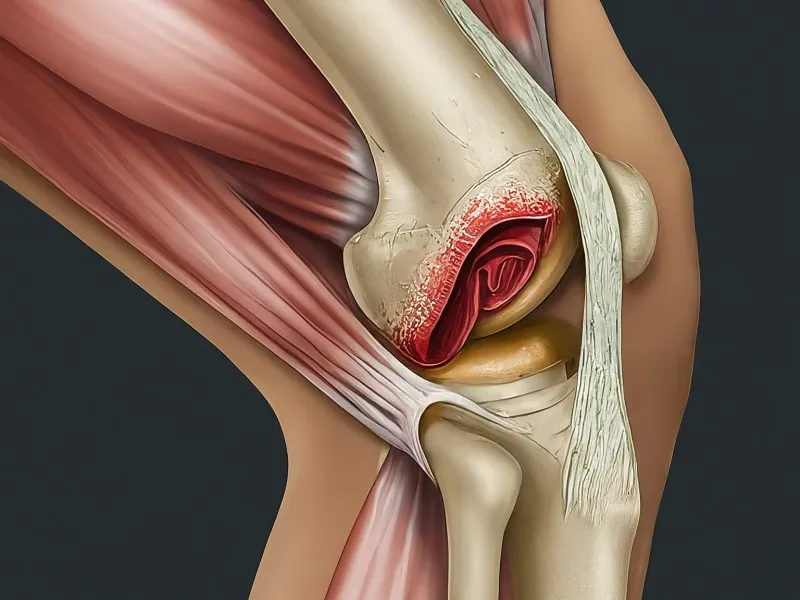

The ACL is one of the four main ligaments in the knee and connects the thigh bone to the shin bone. It is crucial for maintaining knee stability. An ACL tear can range from a mild sprain to a complete rupture. Diagnosis typically begins with a physical examination and may be confirmed with imaging tests such as MRI. Common indicators include the Lachman test and the pivot shift test. Diagnosis of an ACL tear is crucial for opting for the right treatment plan—whether it’s surgical or non-surgical.

A torn ACL can severely impact a person’s mobility and quality of life. The immediate effect is usually marked by discomfort and restricted movement. Untreated ACL tears can lead to further injuries, such as meniscal tears and damage to other ligaments like the posterior cruciate ligament. Over time, the condition can lead to chronic instability and even osteoarthritis. Addressing an ACL tear promptly is vital to prevent more severe complications.